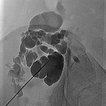

Ultraschallgesteuerte Punktion des zystischen Anteils der LM während der Sklerosierung. Über diese Punktionsnadel wird die LM zunächst kontrastiert, anschließend aspiriert und das Sklerosierungsmittel eingebracht.

Übersichtröntgenbild im Bereich der rechten Beckenschaufel nach Injektion von Kontrastmittel über die in der LM liegende Nadel. Es kontrastieren sich aus dieser Nadellage weite Anteile der LM, damit optimale Position für die Sklerosierung.

Erneute Punktion ca. 5 cm weiter kranial in ein weiteres Kompartment der lymphatischen Malformation. Dieses Kompartment der LM kommuniziert nicht mit dem weiter unten noch sichtbaren Anteil der LM. Es muss daher extra punktiert und sklerosiert werden um die gesamte LM erfolgreich zu sklerosieren.

Erneute Sklerosierungstherapie in einer zweiten Sitzung in Direktpunktionstechnik unter Ultraschallsteuerung in die restlichen zystischen Areale der LM (Röntgenübersichtsbild nach KM-Injektion über die Nadel). Nach Anspritzen von Kontrastmittel wird die restliche LM möglichst vollständig entleert. Erneute Sklerosierungstherapie mittels Picibanil (OK-432).

Makrozystische lymphatische Malformationen (LM), die direkt an der Haut liegen, können durch den hohen lokalen Lymphdruck zu einem Durchtritt von Lymphflüssigkeit durch die Haut über kleine Hautbläschen (Lymphvesikel) führen. Diese Areale werden Lymphangioma circumscriptum genannt. Durch eine Sklerosierungstherapie (hier mit Picibanil = OK-432) werden die Lymphkanäle über eine starke lokale Entzündung verschlossen und die Haut abgedichtet. Günstig in diesem Fall die größeren Anteile der lymphatischen Malformation, die miteinander kommunizieren (nach Injektion von KM über die Punktionsnadel sichtbar). Daher sind nur wenige Punktionen notwendig um die gesamte lymphatische Malformation zu sklerosieren. Dieses minimalinvasive Verfahren ist meist auf Dauer schonender als offen operative Maßnahmen, da einzelne, auch kleine Kammern in den oft fuchsbauartig verzweigten LM mit dem flüssigen Sklerosierungsmittel leicht erreicht werden können.